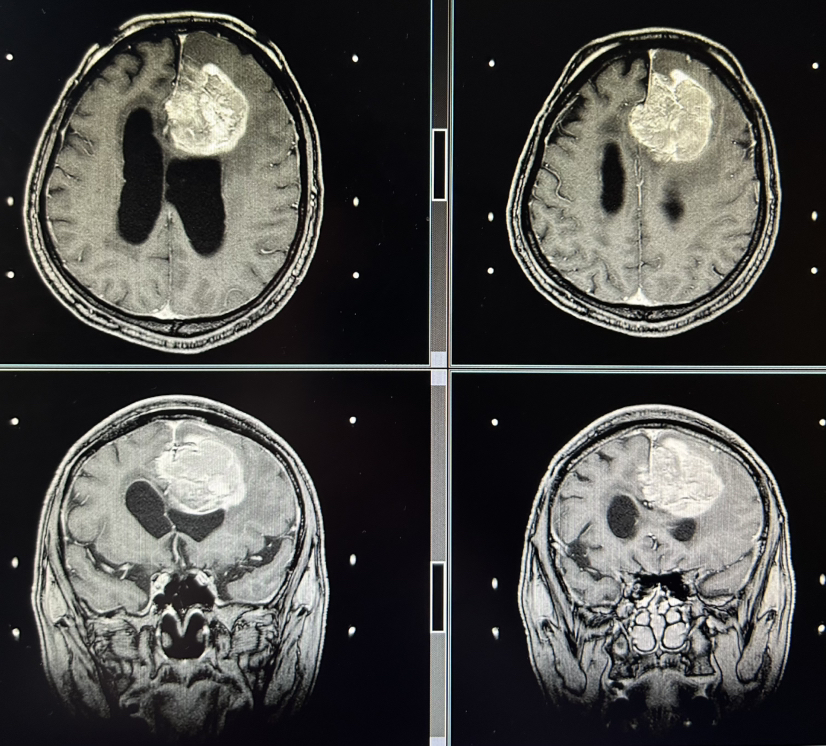

左额叶-胼胝体肿瘤卒中 侵犯对侧额叶 急诊开颅切除 镜下全切